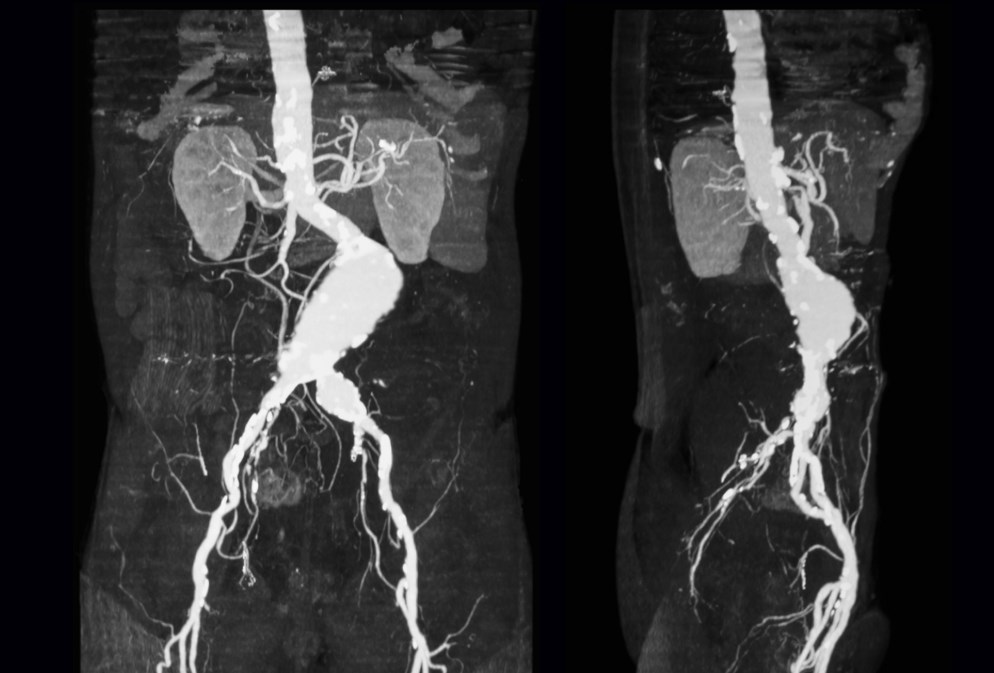

Компьютерная томография брюшной аорты — это современный метод диагностики, который позволяет врачу оценить состояние крупнейшего сосуда организма, его ветвей и прилегающих тканей. От того, насколько правильно выполнена подготовка к КТ брюшной аорты, напрямую зависит точность снимков и информативность исследования. Ниже представлена пошаговая инструкция, которая поможет подготовиться к процедуре спокойно и без лишнего напряжения.

Во время КТ аппарат фиксирует различия в плотности тканей с высокой точностью. Газы в кишечнике, остатки пищи или несоблюдение рекомендаций перед процедурой могут ухудшить визуализацию сосудов и затруднить расшифровку результатов. Подготовка к КТ брюшной аорты особенно важна, если планируется проведение исследования с контрастированием.

КТ аорты с контрастированием позволяет более точно оценить просвет сосуда, стенки аорты и кровоток. Подготовка к такому исследованию имеет дополнительные особенности.

Бесконтрастное КТ позволяет оценить общие анатомические структуры, наличие аневризм и кальцинатов. КТ с контрастом (внутривенное введение йодсодержащего препарата) дает возможность детально изучить просвет сосуда, его стенки, кровоток, а также выявить расслоение, тромбы и атеросклеротические бляшки.